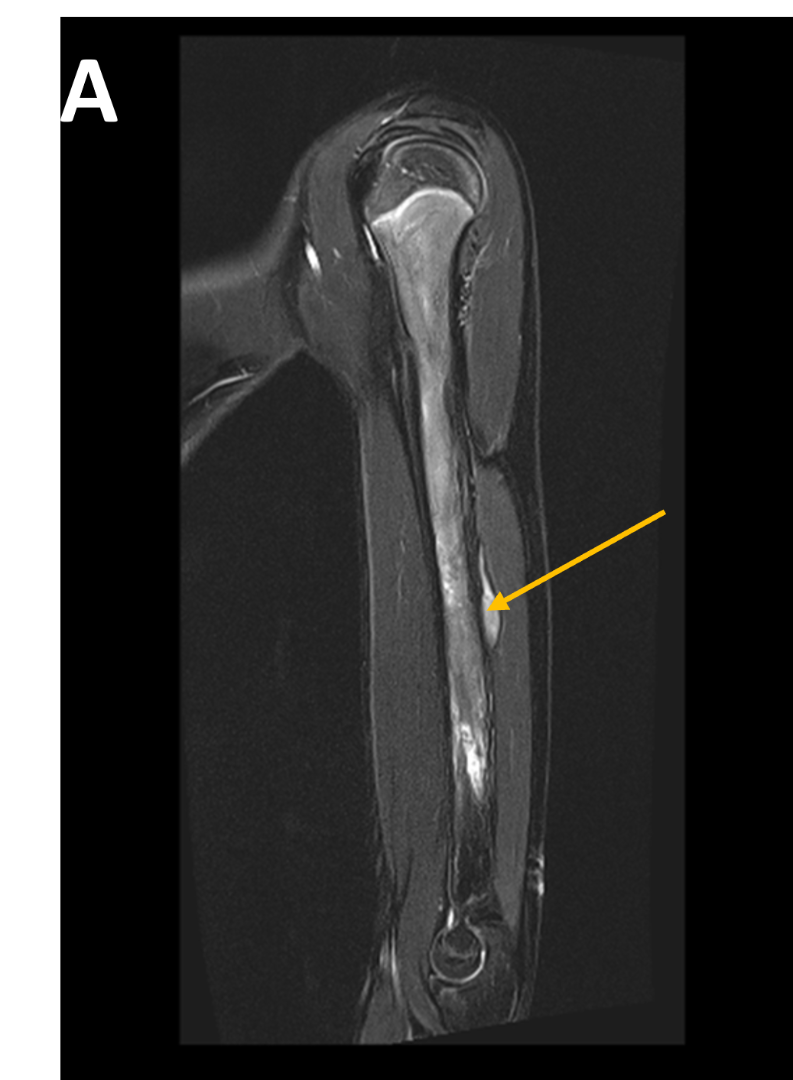

- (A,B) : MR LEFT FOREARM

- A : MR LEFT FOREARM : Fusiform thickening of radial nerve in the posterior compartments of mid-distal 1/3rd arm, as its winds around the spiral groove of the humerus, before piercing the lateral intermuscular septum.